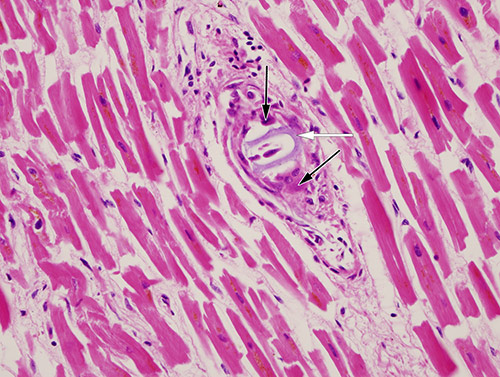

Ved mikroskopisk undersøkelse av hjertemuskulaturen fant man flere små intramurale arteriegrener okkludert av et basofilt fremmedlegememateriale slik pilen på bildet viser. I de fleste affiserte karene var det flerkjernede kjempeceller rundt materialet (svarte piler). I noen kar var det også en mer utbredt betennelsesreaksjon med lymfocytter og plasmaceller rundt de flerkjernede kjempecellene. Funnet passet med hydrofile polymergelemboluser (1, 2).

Polymerbelegg brukes på ulike intravaskulære instrumenter, inkludert katetre og medikamentavgivende stenter, blant annet for å gjøre manipulasjon enklere, og det er antatt å bidra til å redusere komplikasjoner (1). Bruk av polymerbelegg er imidlertid ikke risikofritt, det kan løsne og gi emboluser. Det er beskrevet funn av polymergelemboluser i flere forskjellige organer (1, 3), og det kan føre til alvorlige komplikasjoner som lungeinfarkt, hjerneslag, arytmier og til og med dødsfall (1). Polymergelemboluser i små intramurale arteriegrener i hjertet er en sjelden komplikasjon, men er også beskrevet i litteraturen (4). Selv om stenttrombosen ble ansett som den umiddelbare dødsårsaken hos vår pasient, kan man etter vår oppfatning ikke se bort fra at fremmedlegemeembolusene kan ha hatt betydning.